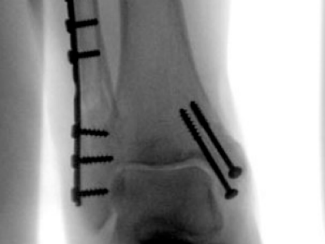

Internal fixation involves the surgical placement of screws, plates, rods, or wires directly onto or within the bone to stabilize the fracture. This technique is often used for more severe fractures, such as displaced or unstable fractures.

Internal fixation refers to the method of physically reconnecting the bones. This might involve special screws, plates, rods, wires, or nails that the surgeon places inside the bones to fix them in the correct place. This prevents the bones from healing abnormally. The entire operation usually takes place while you are asleep under general anesthesia.

Screws and plates are used to hold bone fragments together. Plates are attached to the surface of the bone with screws to maintain alignment.